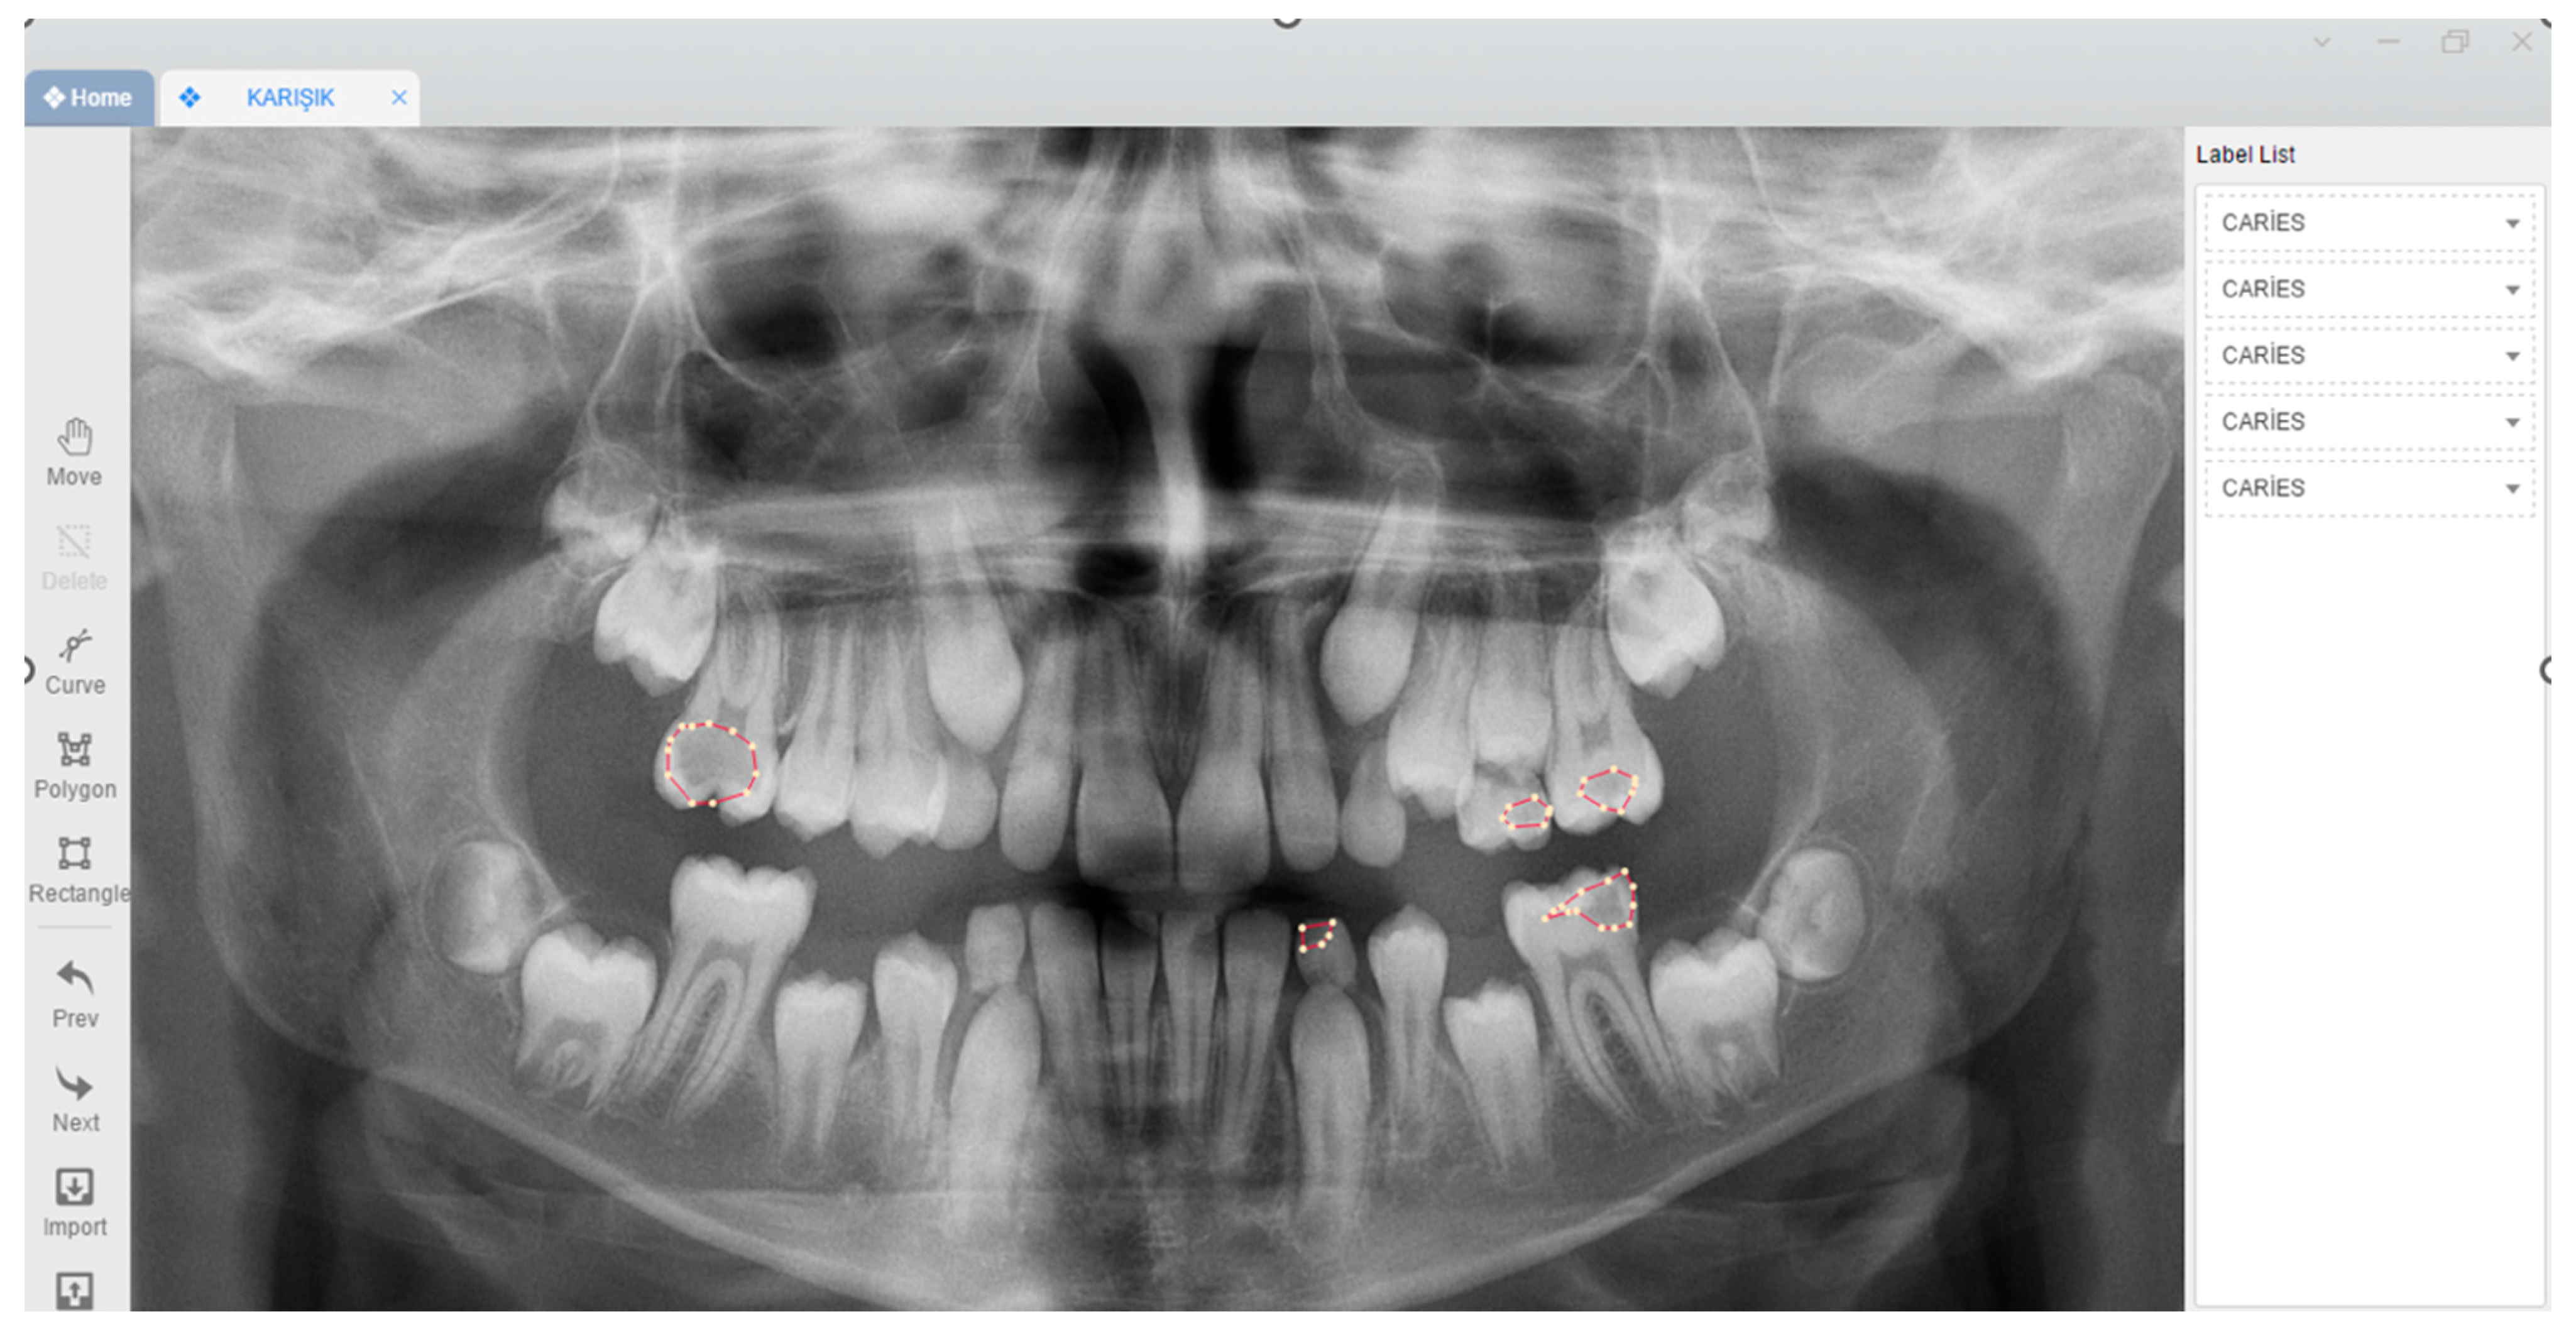

2.3. Image Evaluation